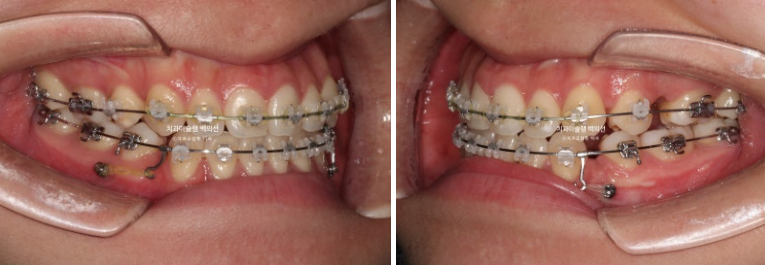

위 앞니는 최대한 뒤로 들어가지 않도록 유지하면서, 아래 앞니는 최대한 뒤로 많이 넣기 위해 아래에 교정용 나사를 2개 심었습니다.

25.08

약 3달간 디테일한 조정을 거쳐 드디어 25년 10월, 치료를 마무리 했습니다.